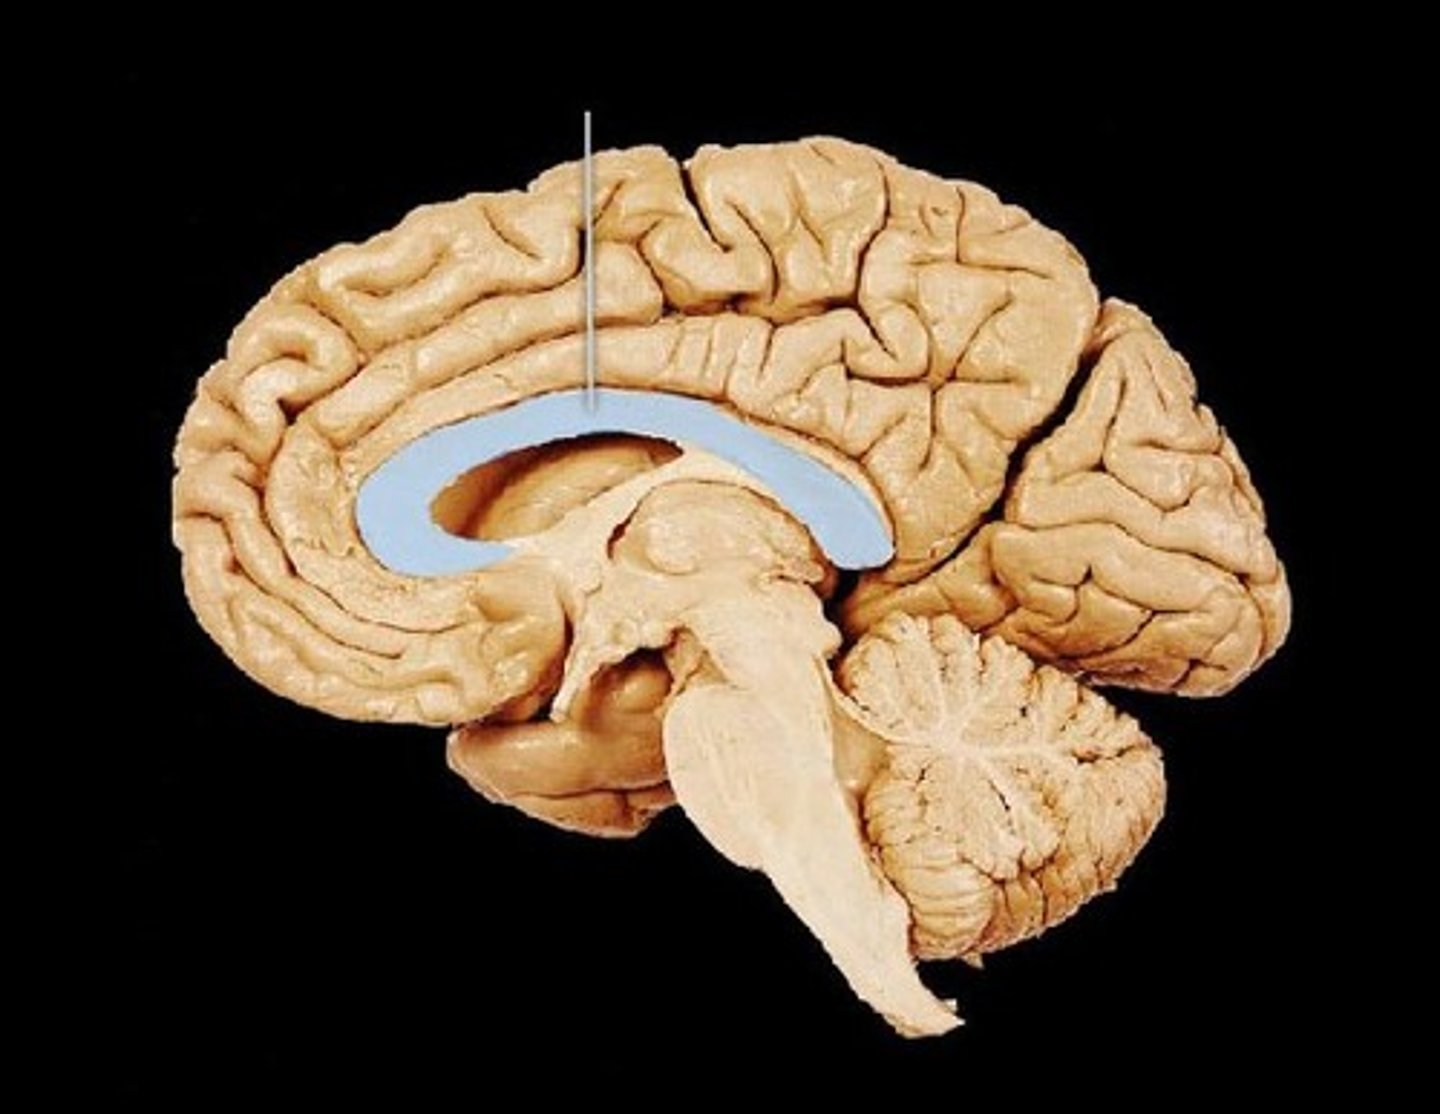

corpus callosum

the large band of neural fibers connecting the two brain hemispheres and carrying messages between them

septum pellucidum

membrane that separates lateral ventricles